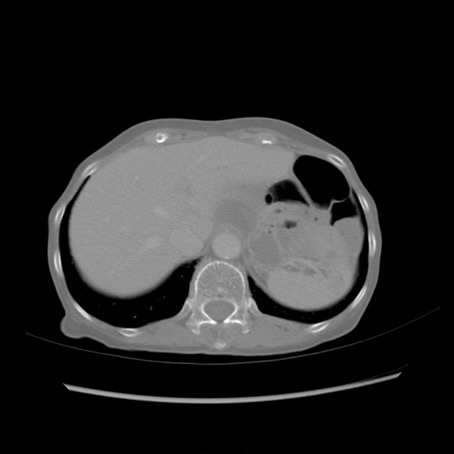

症例25(横断像)

【症例】80歳代女性

【主訴】胸のつかえ感

【現病歴】約9時間前に食後から胸のつかえた感じあり、嘔吐あり、来院。

【既往歴】胃癌(全摘)、胆摘、虫垂炎

【身体所見】心窩部に圧痛あり、反跳痛なし。

【データ】WBC 5700、CRP 0.05